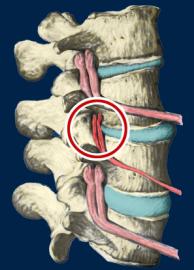

Subluxation Degeneration This is a representation of one type of subluxation. A subluxation, as defined by the Association of Chiropractic Colleges is: "A subluxation is a complex of functional and/or structural and/or pathological articular changes that compromise neural integrity and may influence organ system function and general health." When a subluxation occurs it causes nerve interference in some portion of the body affected by those nerves. The subluxation causes changes to the structure as well as the nerves. These changes get progressively worse as time is allowed to work on the subluxated area of the spine. These changes take the form of ongoing degeneration known as "subluxation degeneration". By understanding the type and amount of changes, it is possible to reasonably estimate the time subluxations have been present in a spine. Having this information is useful in understanding the time and effort needed for correction.